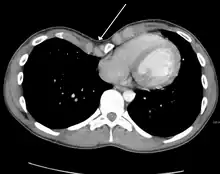

Many scales have been developed to determine the degree of deformity in the chest wall. Most of these are variants on the distance between the sternum and the spine. One such index is the Backer ratio which grades severity of deformity based on the ratio between the diameter of the vertebral body nearest to xiphosternal junction and the distance between the xiphosternal junction and the nearest vertebral body.[17] More recently the Haller index has been used based on CT scan measurements. An index over 3.25 is often defined as severe.[18] The Haller index is the ratio between the horizontal distance of the inside of the ribcage and the shortest distance between the vertebrae and sternum.[19]

Chest x-rays are also useful in the diagnosis. The chest x-ray in pectus excavatum can show an opacity in the right lung area that can be mistaken for an infiltrate (such as that seen with pneumonia).[20] Some studies also suggest that the Haller index can be calculated based on chest x-ray as opposed to CT scanning in individuals who have no limitation in their function.[21]